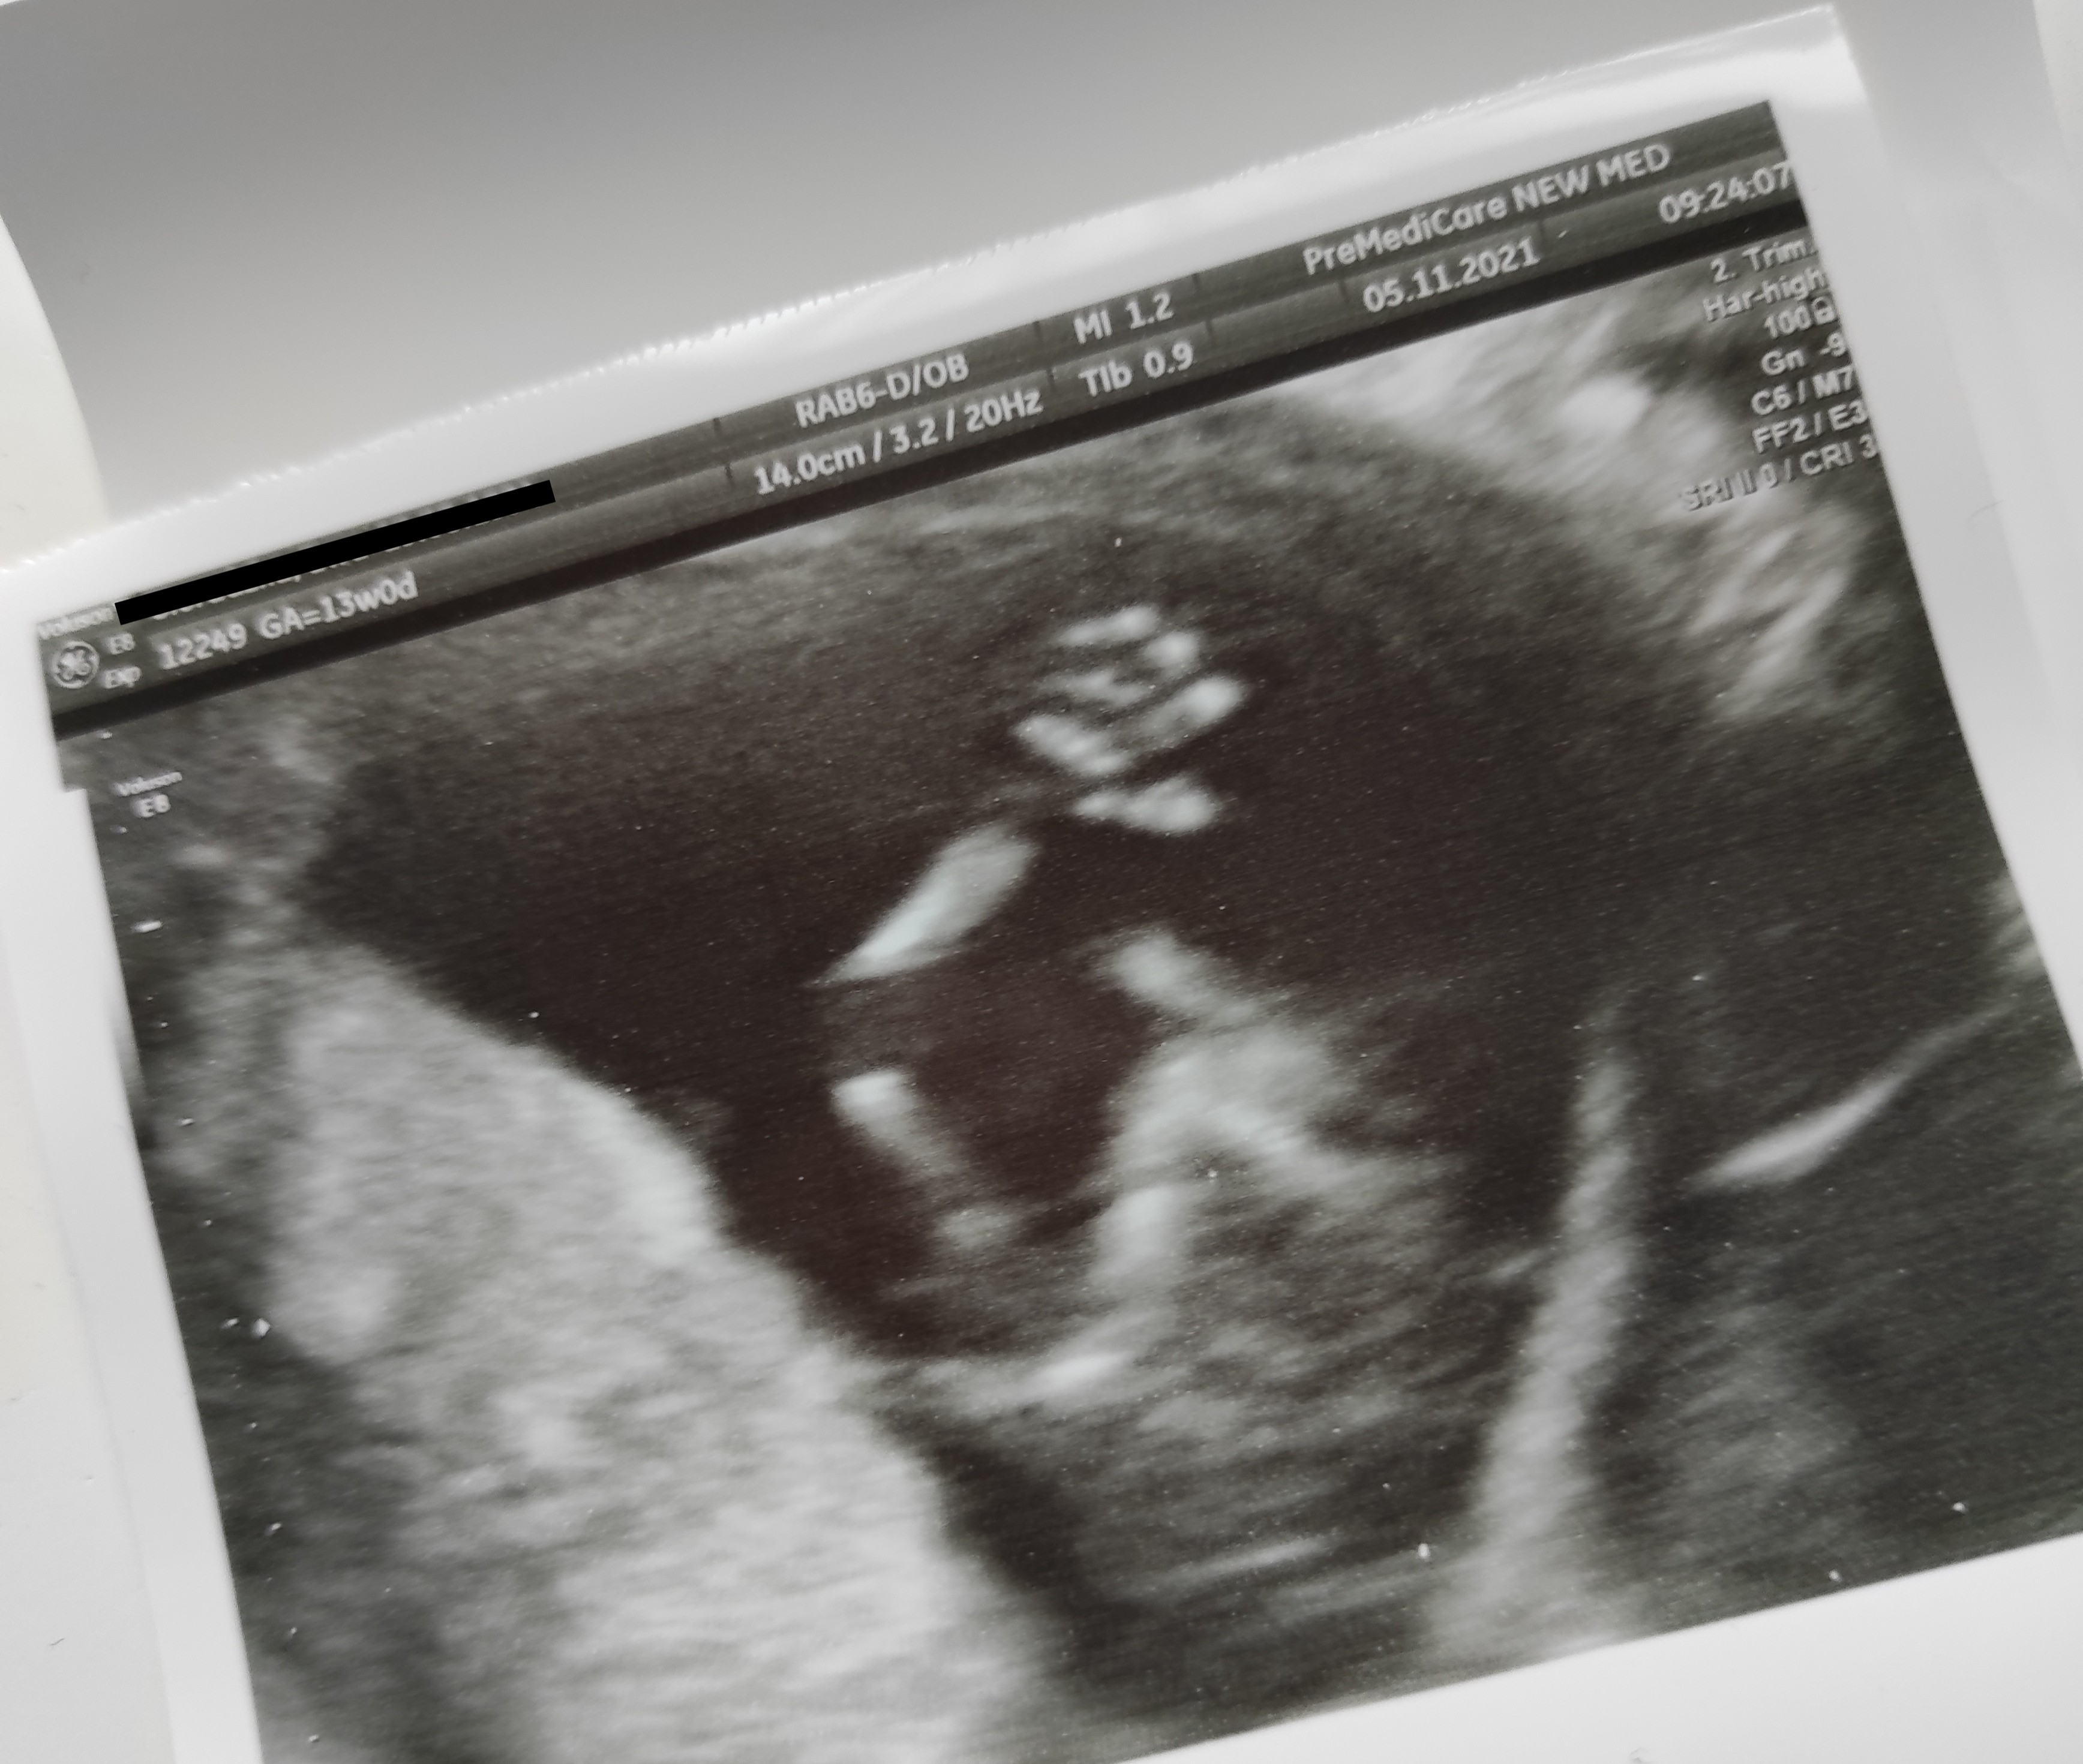

Dziewczyny jestem po prenatalnym, wszystko jest wporządku ,pomiary nie wzbudzają wątpliwości , dzidzia zdrowa przezierność i kość nosowa super 😊 płeć na razie nie jest bliżej określoną bo na początku lekarz był skłonny rzec ,że to chłopiec natomiast później trochę zwątpił i ostatecznie mówi że nie jest pewny żeby się nie nastawiać na razie, więc mamy ktosia 😁

Zdjęcie wstawię na wątek USG 😊

Załączniki

• IMG_20211105_113533.jpg

IMG_20211105_113533.jpg

1,1 MB · Wyświetleń: 107